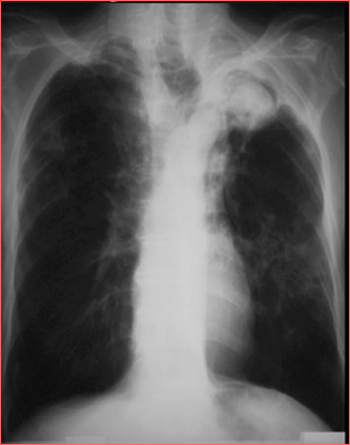

DESCRIERE:

pe tot teritoriul pulmonar, bilateral → multiple opacități micronodulare diseminate, de intensitate mare

la niv. hilului drept → opacitate policiclică (blocuri adenopatice)

DX: miliara TBC

DD:

miliara carcinomatoasă

bronhopneumonie

→ distribuție predominant bazală, noduli de dimensiuni mai mari, fără ADP